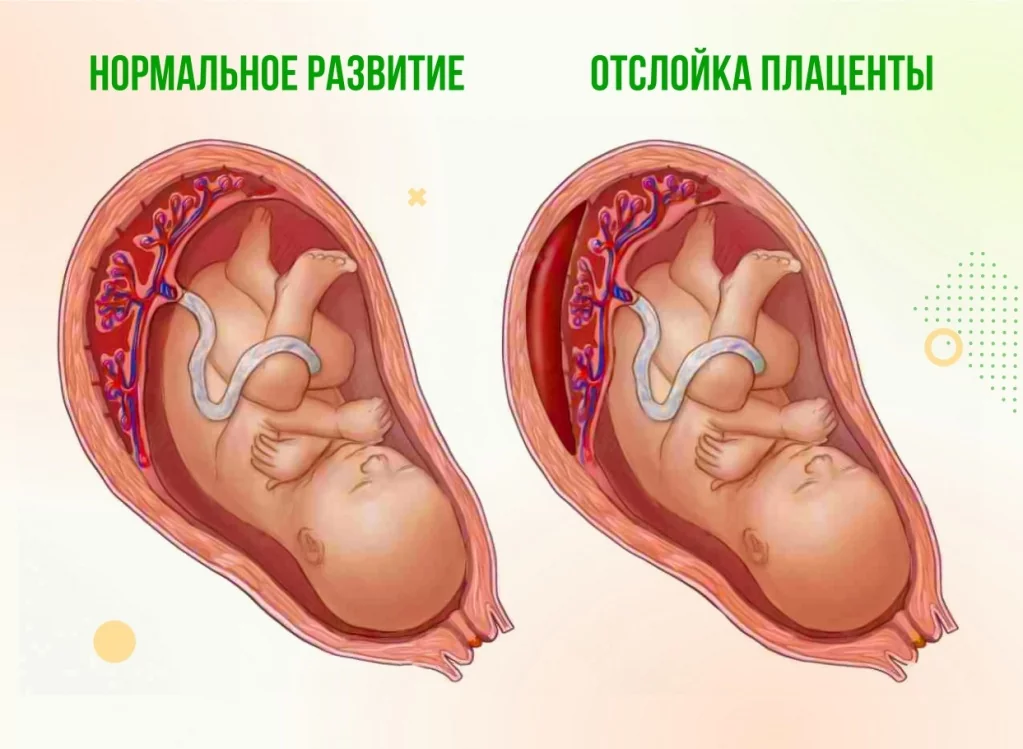

Околоплодный пузырь и плацента: структура и функции